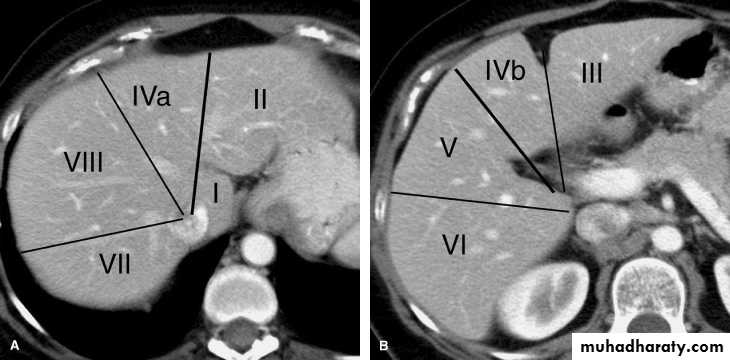

CT scan